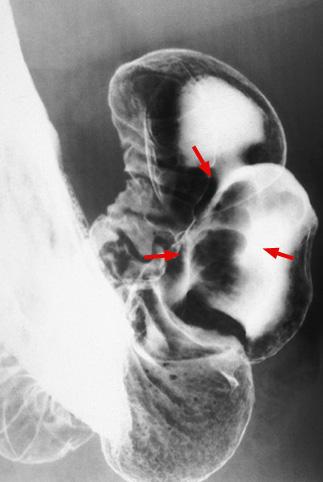

疾病(病理主体)的分类肿瘤样病变/其他

部位(按器官分)胃(部位)/前庭

检查方法X线

肿瘤最大直径30~34